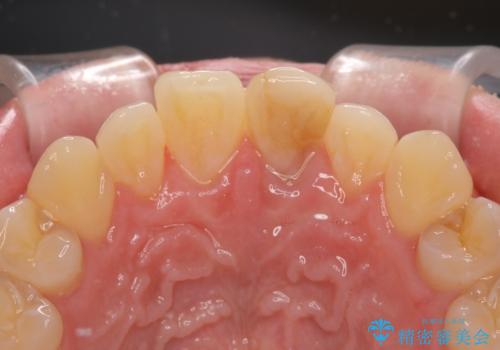

変色した前歯をオールセラミッククラウンに

- 転んだ際に欠けてしまった前歯の変色が気になるとのことで来院された患者様です。

診察やレントゲン写真より神経組織の失活が認められたため、根管治療、ファイバーコアによる土台築製後、オールセラミッククラウンにて補綴することとしました。

神経を取り除いた歯は時間とともに変色してきます。

クリーニングやホワイトニングでは改善できないため、オールセラミッククラウンなどによる補綴治療が必要となります。